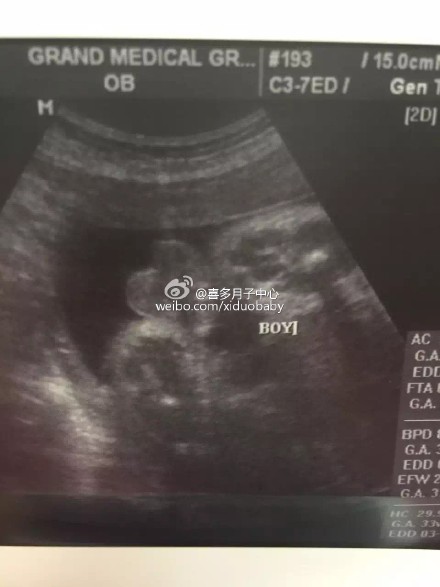

【孕妇妈妈对美国医生医院的评价】入住在洛杉矶喜多月子中心Rancho cucamonga别墅的北京赴美生子孕妈最近来到医院进行产检,并知晓了宝宝的性别,是个小男生,妈妈对美国这边的服务以及设施等方面都很满意,很安心顺畅的美国生子之行,祝妈妈一切顺利!